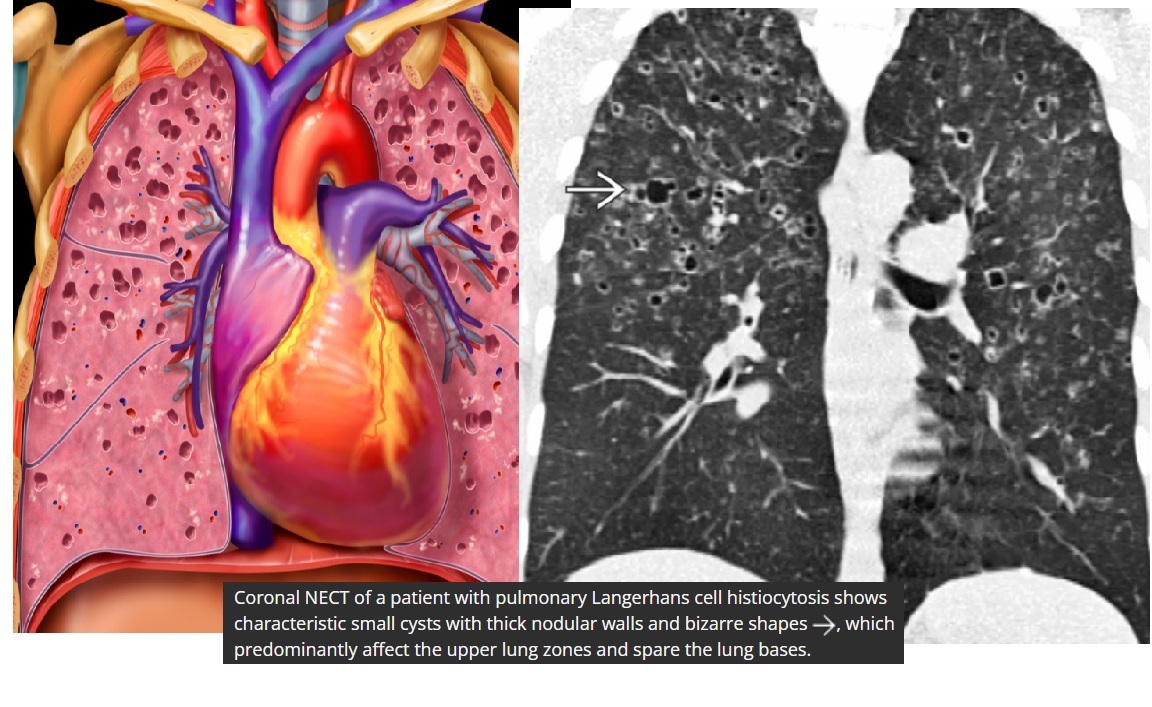

Angioinvasive aspergillosis

Halo sign

=Nodule/mass/consolidation surrounded by ground-glass opacity related to hemorrhage

Air crescent sign

=Crescent-shaped gas collection within nodule, mass, or consolidation

heralds improvement in the condition.